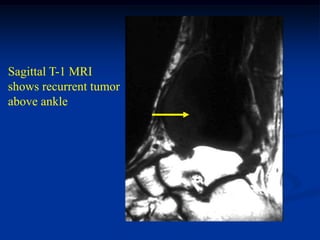

symptoms of ankle pain

Turns HIV positive

One year later with

osteopenia about

painful and swollen

ankle

Sagittal T-1 MRI

shows recurrent tumor

above ankle